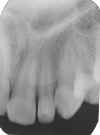

ANOMALIAS

1